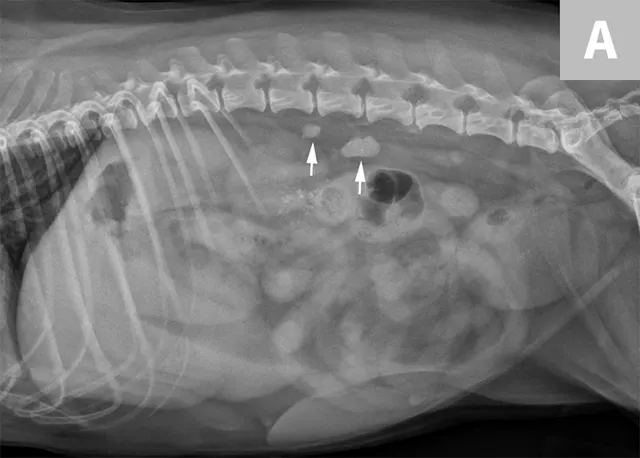

FIGURE 11A

Lateral radiograph of a male dog collimated to include the urinary bladder and os penis. Note the well-defined mineral opacity just proximal to and at the same level as the base of the os penis—a separate center of ossification (arrow). Also note the two soft tissue opaque nodules summating with the prepuce, presumed to be small nipples (arrowheads).